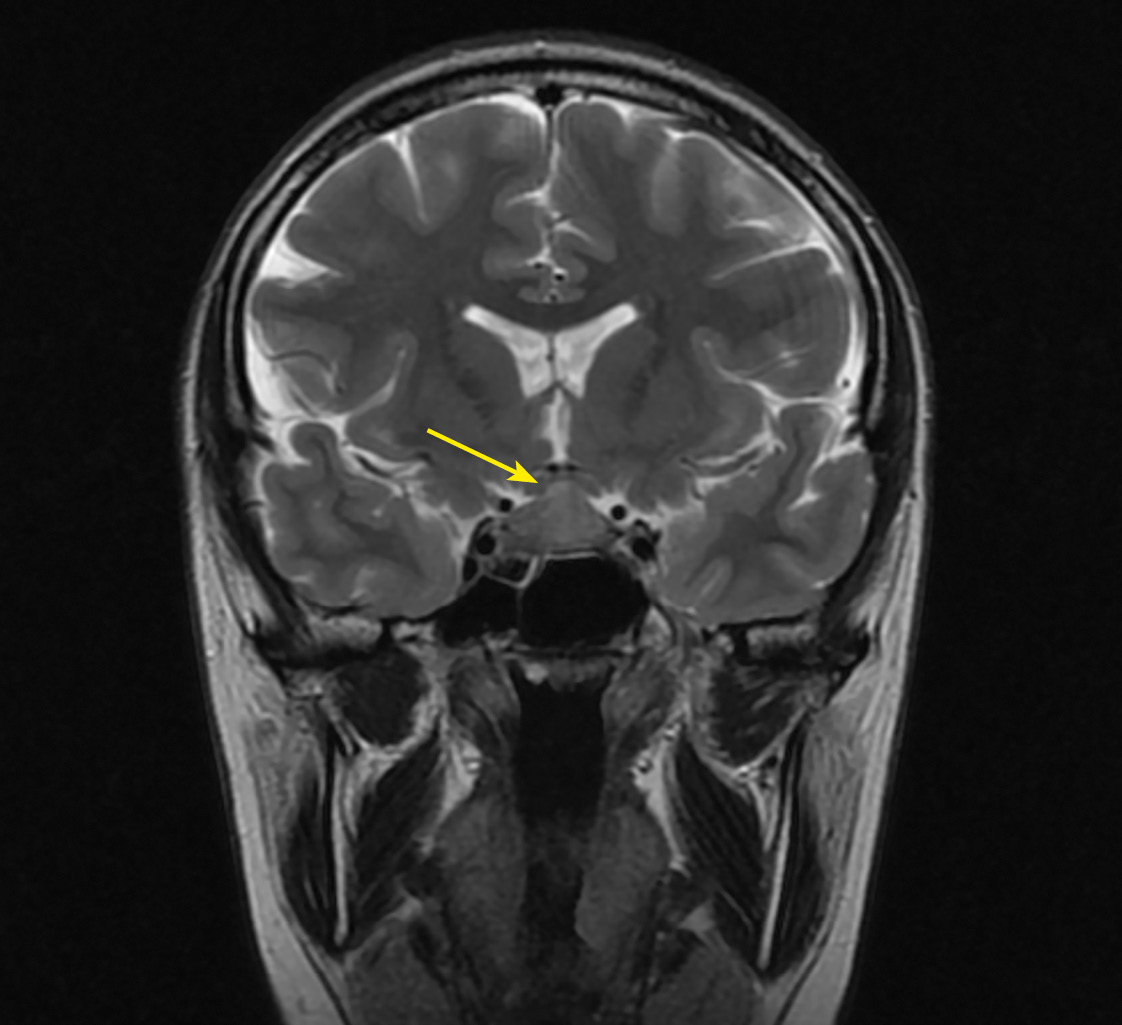

В рамках обследования по поводу головных болей и нарушения полей зрения на 17–18 неделе беременности пациентке выполнена МРТ головного мозга без контрастного усиления, по результатам которой выявлены признаки аденомы гипофиза размерами 10x15x20 мм с супраселлярным ростом и умеренной компрессией хиазмы, нейрогипофиз не дифференцировался (рис. 1, 2).

Рисунок 1. МРТ головы без контрастного усиления, Т2-взвешенное изображение,

коронарная (фронтальная) проекция.

МР-картина «аденомы» гипофиза размерами 10x15x20 мм

с супраселлярным ростом и умеренной компрессией хиазмы (изменения указаны стрелкой).